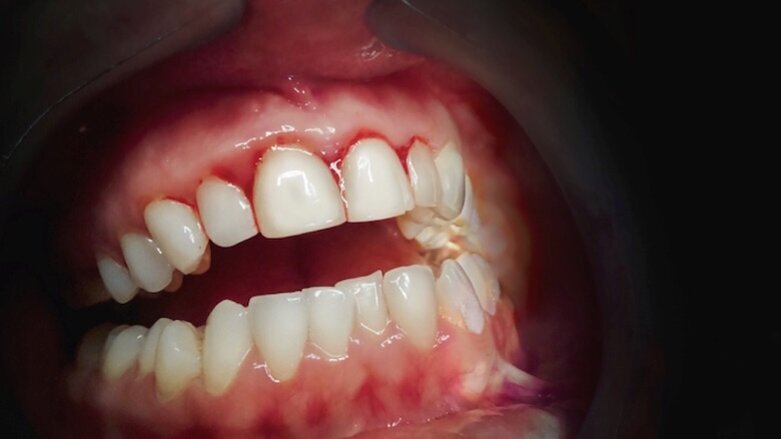

En un estudio realizado en 2018 comparando diferentes técnicas hemostáticas en cirugía, donde una de ellas era solamente la realización de sutura y la segunda, sutura y colocación de cemento quirúrgico, se concluyó que en el grupo donde la sutura fue acompañada del cemento quirúrgico la cirugía resultó menos dolorosa para el paciente, en un seguimiento de dos semanas, tomando en cuenta que un factor importante fue también el tamaño del lecho quirúrgico2.

Existe también controversia entre el tipo de cemento quirúrgico a utilizar, si cemento con eugenol o cemento que no contenga eugenol. En un estudio realizado en 2018, con 12 pacientes con periodontitis que necesitaban cirugía periodontal, se dividió en 2 grupos, uno donde se utilizó cemento fotocurado (con eugenol) y en el segundo, cemento sin eugenol. No hubo diferencias significativas en la rapidez de la sanación de la herida, pero se pudo determinar que en el cemento sin eugenol hay un mayor acúmulo de placa y por ende mayor desconformidad al paciente3.

En la Universidad de Hamadan, se quiso evaluar factores como inflamación, dolor e infección en pacientes a los que se les aplicaba CQ y a los que no se les aplicaba. En un estudio con 33 pacientes de 7-14 días, se determinó que no tuvieron diferencias significativas en el color de la gíngiva, inflamación o infección, pero sí hubo relevancia en el dolor. Los pacientes a los que se les aplicó el CQ relataron menos dolor que los que no5.

El CQ fue evaluado luego de la realización de alargamiento de corona en 36 pacientes, y se halló recesión gingival en el 57.8% del grupo control (a los que no se les aplicó el cemento quirúrgico) y solo un 5.5% a los que sí6.